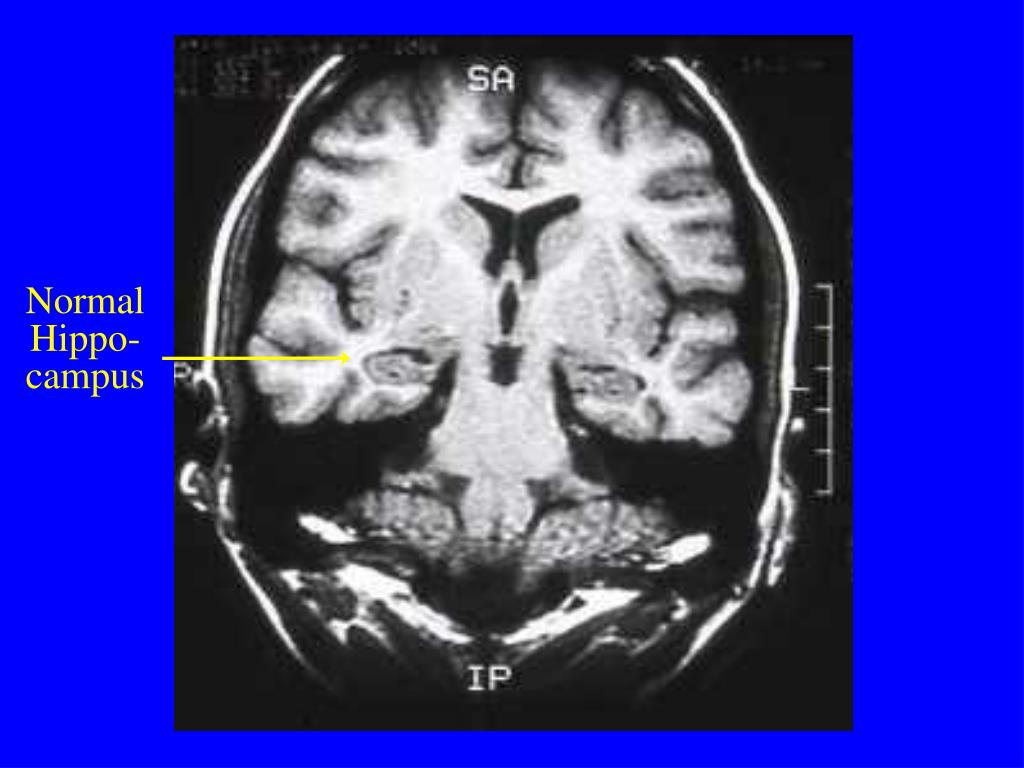

19. Normal Hippo- campus

20. Atrophic Hippo-campus in AD 62 year old woman with rapid progression of memory loss

16. Landmarks (Cont.) • Internal capsule—anterior and posterior limbs • Thalami • Sylvian fissures • Sagittal views • Severity of cortical atrophy • Corpus callosum and cingulate gyrus • Pituitary • Coronal views • Hippocampus and amygdala